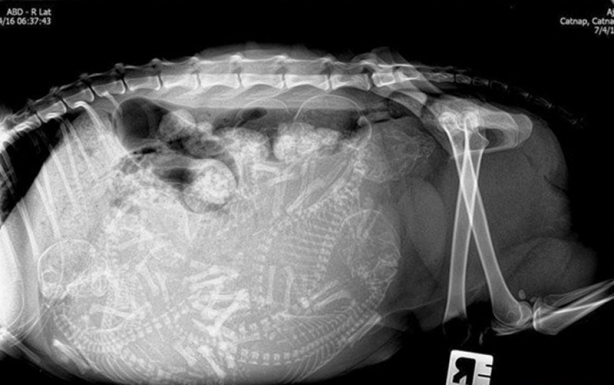

Hamile bir kedi ve onun röntgen filmi.

Hamile kedi

Hamile bir kedi daha